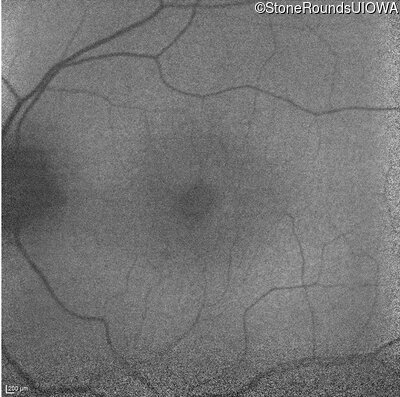

OD

OS

20/200 sc

10/160 -1 sc

Age at visit:

56 years